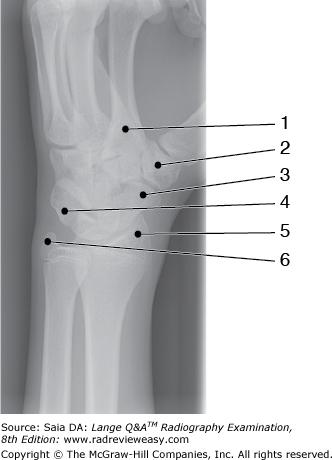

Which of the labeled bones in Figure A identifies the tarsal navicular?

Number 6

Which of the labeled bones in Figure 6–14 identifies the tarsal navicular?

What does the number 8 in Figure 6–14 identify?

Medial malleolus